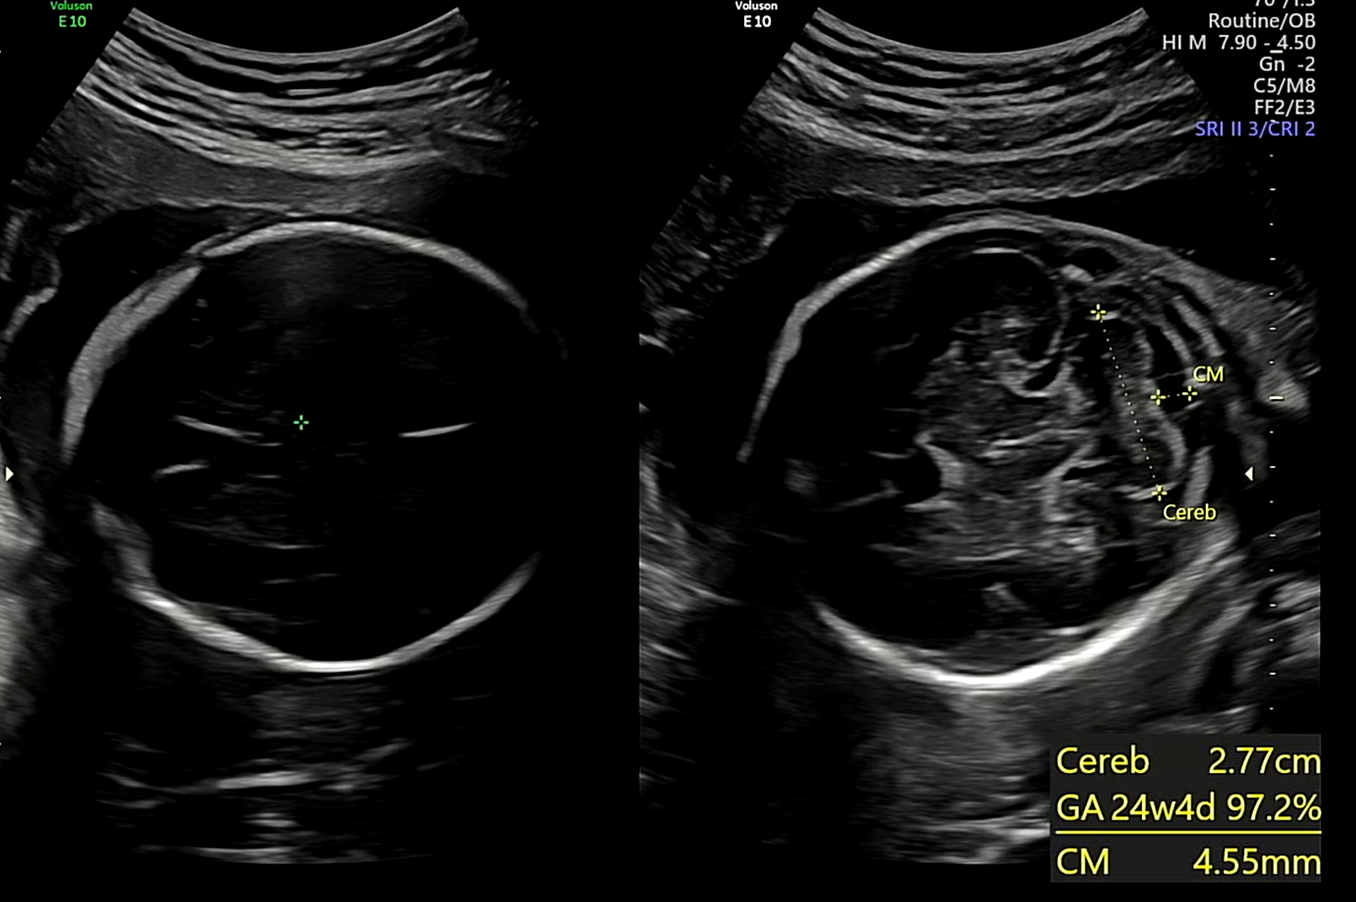

※ 초음파 용어) Cereb : 소뇌 장축 길이 , CM : 숨뇌 길이

뇌크기 또한 적정 수준에 맞게 잘 성장하고 있음을 초음파를 통해 알 수 있었다.